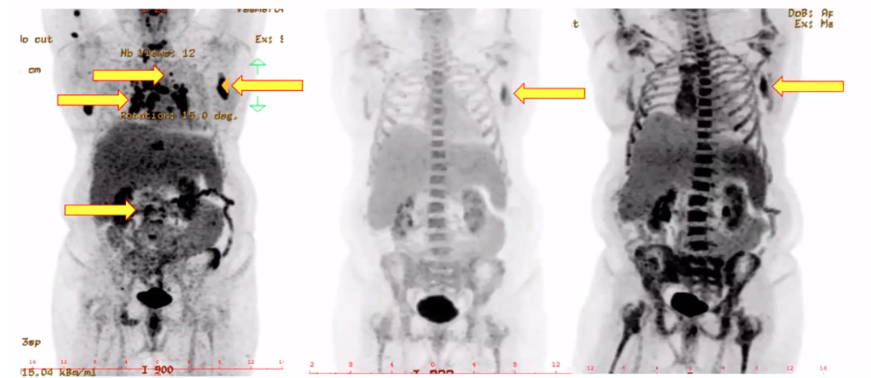

➤一位60岁患者,原发难治的高级别B细胞淋巴瘤(双表达,三打击),伴MYC、BCL-2和BCL-6重排,c-MYC(约40%+)、BCL-2(90+),同时P53(+),Ki67(95%+);GCB型,IV期B组,IPI指数4分(高危组),CNS-IPI 4分(高危组),伴严重感染。

➤患者外院2个疗程的标准治疗后状态很差,PS 4分,只能卧床,不能经口进食。

病例分析及治疗方案选择:

➤该患者前期治疗效果不佳,状态极很差,且为原发难治的高级别B细胞淋巴瘤(双表达,三打击),极高危、预后差、肿瘤易复发。

➤基于Pola+BR方案GO29365研究及真实世界的研究数据表现出的显著疗效,以及不良反应较轻。本院通过同情给药给予Pola+BR为基础的联合方案治疗。

➤4个疗程后PS评分得到显著改善(从4分到1分),肿瘤和感染均得到很好控制,遂进行淋巴细胞采集,为CAR-T治疗做准备。在等待CAR-T回输期间,为避免病情反弹,继续进行第5的疗程的Pola联合治疗,患者达到PMR。之后进一步控制感染情况,同时继续进行第6个疗程Pola联合治疗避免病情反复,并等待CAR-T回输。Pola联合方案起到了很好的减瘤作用,患者CAR-T回输后疗效评估达CMR,且不良反应较少。